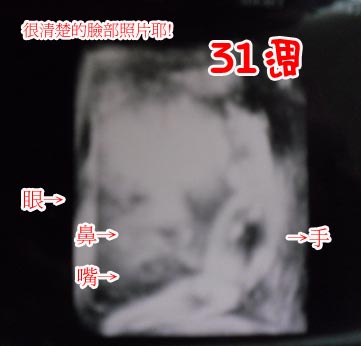

31週的產檢~寶寶的臉好明顯喔^^可是不知道是像誰呢^^

可愛的眼睛鼻子嘴巴跟小手手~嘿嘿~不管像誰都一樣可愛